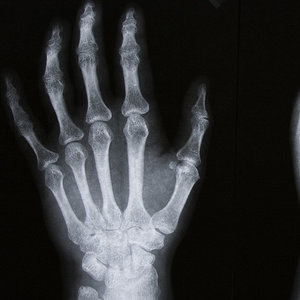

Trudniejsze są dwie pozostałe postaci choroby. W przypadku układowego młodzieńczego zapalenia stawów można powiedzieć, że jest to najcięższa postać choroby, ponieważ atakuje różne stawy, narządy, w tym tak ważne jak serce albo oczy.Wielostawowe młodzieńcze zapalenie stawów jest nieznacznie lżejsze niż wspomniany wyżej rodzaj, jednak również powoduje znaczący problem w funkcjonowaniu, gdyż dotyka zazwyczaj powyżej 5 stawów, w tym palców dłoni i stóp.

Pierwszym objawem pojawienia się choroby może być sztywność stawów po przebudzeniu, która nie powinna pojawiać się u osób młodszych. Za drugi objaw można uznać dolegliwości bólowe, choć początkowo nie wiązane ze stawami. Zdarza się, że początek zachorowania lub już poważniejszy rozwój choroby daje takie objawy, jak gorączka, wysypka na klatce piersiowej, obrzęk węzłów chłonnych. Zdarza się, że objawy pojawiają się i znikają, ale nie jest możliwe do określenia, czemu choroba w ogóle rozwija się u młodych ludzi i pomimo przeprowadzonych badań nie ma jednoznacznej odpowiedzi na to pytanie.